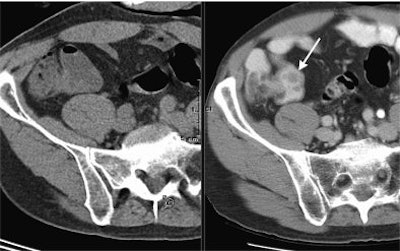

![]() |

| The diagnostic CT image (top) shows a patient with colorectal cancer with hepatic metastasis in the left hepatic lobe (arrow), but it is not on PET/CT (above). The corresponding PET image (below) confirms metastasis. The study notes that treatment was not changed, as it was seen by PET scan. "Limitations of CT during PET/CT" (Journal of Nuclear Medicine, Vol. 48:10, pp. 1583-1591). Reprinted by permission of SNM. |